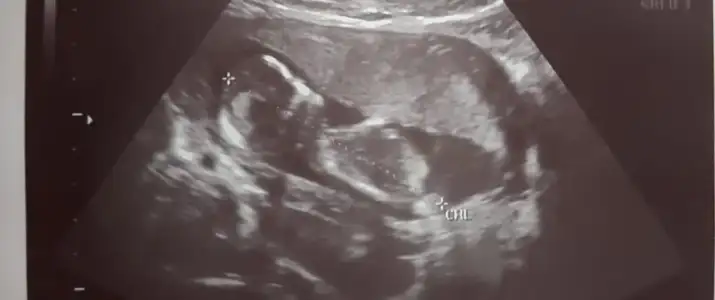

Kız görünüyor ☺️

Çok teşekkür ederim cevap verdiğiniz için netleşince anketi oyşayacam inşallah ama keşke kız olsa 2 oğlum var ama işte sağlıklı olsun hayırlısı diyelim

Belkide kızdır çünkü çıkıntı gördüğüm nub ise erkek sanki dedim başka USG varmi